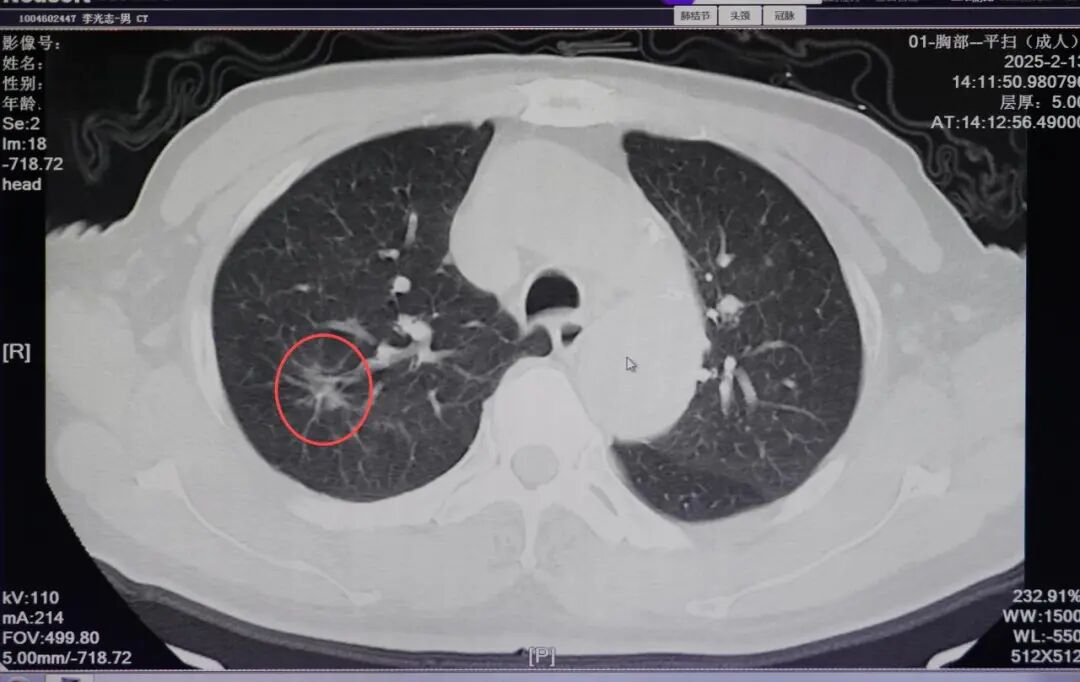

2月21日,贵州航天医院国务院政府特殊津贴专家、二级教授、学科带头人廖江荣教授呼吸团队再次为一名81岁的患者成功实施AI机器人辅助经皮穿刺氩氦刀冷冻消融术,仅用40分钟就完成对肺结节的“精准狙击”。 “AI机器人不仅提供高精度的穿刺方案,还能通过机械臂稳定执行,避免人工操作的手部震颤误差。”廖江荣教授介绍。 传统经皮穿刺氩氦刀冷冻消融术高度依赖医生经验,面对复杂病灶时,常面临“定位难、穿刺深、耗时长”的挑战。在此次手术中,呼吸团队借助AI机器人智能影像分析、穿刺计划系统,对患者肺结节进行了多视角的立体三维重建,精确定位了病灶,并规划出最佳进针位置、角度和轨迹,通过AI机器人可视影像系统和机械臂穿刺系统的引导,“一针”就穿刺进入病灶预定位置进行冷冻消融,手术过程仅40分钟。 术 前 机器人机械臂定位中 完成定位 消融针通过机械臂导引孔精准到达病灶位置 冷冻消融中 消融后,晕征范围完全覆盖结节位置 此次接受手术的是一位81岁的高龄患者,肺结节最大径达2.3cm,由于身体条件限制,传统手术风险较高,在AI机器人辅助下的氩氦刀冷冻消融术完成了病灶的精准消融。 什么是AI机器人辅助消融治疗? AI机器人辅助消融治疗术是一种较为先进精准、微创的技术,医生通过AI机器人精密的操作系统,以毫米级的精确度操控冷冻或微波探针,直达靶点,释放低温或高温摧毁病变组织,同时明显提升了手术的安全性和效率。 与外科手术相比,消融治疗的创伤程度要轻许多,极大地减轻了患者的手术痛苦,缩短了康复周期。 与徒手穿刺相比,AI机器人规划和辅助引导定位具有更稳定、更精准、更安全的优势,避免反复调整穿刺方向与深度,造成更多的伤害。 如果病灶靠近肺内大的血管、气管或肺外的重要脏器,AI机器人辅助消融能最大限度避开高危部位,保护周围健康肺组织不受损伤。 什么是氩氦刀冷冻消融? 氩氦刀冷冻消融是通过将一根1.7-3毫米的中空钢针,穿刺进入病灶,先注入氩气,迅速降温至-160摄氏度,冰冻肿瘤数分钟,再注入氦气,快速升温至20-30摄氏度,共历经3个冷冻、复温循环过程,对病灶组织进行物理性杀灭。 主要适用于 2.重要脏器功能不全,体质过弱,不宜手术的患者。 3.术后复发、转移性癌灶、多发癌灶的患者。 4.晚期患者延长生命提高生存质量的姑息性治疗。 5.因各种原因拒绝手术的患者。 贵州航天医院呼吸与危重症医学科微创介入诊疗技术已达到国内前列,省内领先水平,是亚洲冷冻治疗学会常务理事单位,并获批成立遵义市肺结节多学科(MDT)微创诊疗中心。 肺结节MDT门诊出诊信息 出诊时间: 周一至周五 8:00--12:00;14:00--17:00 出诊地点: 遵义市肺结节多学科微创诊疗中心(MDT)门诊(贵州航天医院呼吸综合楼1楼) 呼吸与危重症医学科与心胸外科、医学影像科、麻醉科等科室建立了多学科(MDT)会诊机制,结合患者情况,通过采取外科手术、冷、热消融等多种治疗手段,帮助患者安全、有效、精准、科学、快速治疗肺结节,单次消融手术时间约半小时左右,几乎没有疼痛,且并发症少,3-5天即可出院,有效减少了患者因开刀手术需长时间恢复的痛苦。 注:图片来源于网络,如有侵权,请联系删除。 贵州航天医院 呼吸与危重症医学科专家团队 廖江荣 国务院政府特殊津贴专家 二级教授 主任医师 呼吸与危重症医学科 学科带头人 国家级学术任职: 第二届中国医药教育协会介入微创专业委员会呼吸分会副主任委员 中国抗癌协会肿瘤微创治疗专业委员会常务委员 中国防痨协会结核病转化医学专业分会常务委员 第一届中国人体健康科技促进会呼吸介入专委会常务委员 中国医疗保健国际交流促进会结核病学分会第三届委员会常务委员 中国抗癌协会肿瘤微创治疗专业委员会粒子治疗学组第四届委员会委员 中华医学会结核临床专业委员会内镜介入委员 中华医学会放射学分会第十五届委员会介入学组呼吸系统介入专业委员会委员 北京健康促进会中青年专家委员会胸部疾病精准活检分委会副主任委员 中国医师协会介入医师分会第二届委员会肿瘤消融专业委员会委员 中国结核病防治综合质量控制专家指导委员会委员 亚洲冷冻治疗学会常务委员 世界内镜医师协会呼吸内镜协会常务理事 内镜临床诊疗质量评价专家委员会委员 “西部呼吸介入联盟”副理事长 专业擅长: 呼吸系统(肺)疑难病的诊断及危重病的抢救,呼吸系统(肺)感染性、疑难性疾病介入快速诊断(ROSE),尤其在肺癌、肺小结节早期诊断,肺癌微创综合靶向治疗,难治性、复治性、重症肺结核诊疗,硬质支气管下复杂性气道狭窄诊治,纤支镜介入治疗气道肿瘤、结核、气道狭窄(球囊扩张、支架植入、高频电刀、氩气刀、冷冻、灌洗、注药、微波消融),间质性肺疾病的诊疗上具有极高水平;带领团队勇于创新,在贵州省率先开展多项新技术、新疗法,如CT引导下及纤支镜下I125粒子植入及CT引导下微波、射频消融介入治疗肺癌等多项新技术,带动了贵州省肺部疾病的介入治疗水平提高。 蒋 婷 呼吸与危重症医学科 总负责人 副主任医师 专业擅长:从医20余年,在呼吸系统疾病、介入呼吸病学、肺部结核、肺部肿瘤等方面具有丰富的临床经验和专业技能,尤其是慢性阻塞性肺疾病、支气管扩张、肺结核、耐药肺结核、肺癌、胸腔积液等肺部疾病的诊治、微创介入、危重病患者抢救。 现任中国防痨协会人兽共患结核病专业分会委员,中国女医师协会第一届介入专业委员会委员,贵州省基层呼吸疾病防治联盟-间质性肺疾病联盟委员,贵州省防痨协会第七届理事会理事,贵州省中西医结合学会呼吸专业委员介入呼吸病学组委员,贵州省遵义市中医药学会中西医结合肺病(呼吸)分会副主任委员,贵州省遵义市中医药学会中医肿瘤专业委员会常委;发表论文数篇,参与并主持多项科研项目。 李桂凤 呼吸与危重症医学科 三病区 主任 副主任医师 专业擅长:从事呼吸系统疾病、结核病学、介入呼吸病学、肿瘤综合治疗、呼吸康复等临床工作20余年,擅长呼吸内科常见病、多发病及疑难重症危重病症的诊治,尤其对重症疑难结核及耐药结核病、介入治疗(肺)呼吸系统疾病、呼吸危重病抢救等方面具有较高诊疗水平。 中国防痨协会非结核病专业委员会委员,贵州省中西医结合学会第六届呼吸专业委员会委员,贵州省康复学会睡眠障碍康复专业委员会委员,遵义市呼吸内科医疗质量控制中心委员,遵义市落实民生实事结核病筛查阅片专家组成员;主持及参与实用新型专利3项。 周裕祥 呼吸与危重症医学科 四病区 主任 副主任医师 专业擅长:经皮肺介入、经血管介入诊疗技术。 贵州省中西医结合学会呼吸专业委员会介入呼吸病学组常务委员,中国医师协会呼吸医师分会介入呼吸病学工作委员会呼吸病血管介入学组委员,贵州省中西医结合学会呼吸学分会委员,遵义市医学会放射肿瘤治疗学分会委员,中国医药教育协会介入微创呼吸分会委员,北京健康促进会中青年专家委员会胸部疾病精准活检分委会委员;曾赴重庆医科大学RICU、珠海市人民医院介入科进修学习。 杨 芳 呼吸与危重症医学科 内镜中心 主任 副主任医师 专业擅长:从事临床工作约16年,对呼吸危重病的救治有独到的见解,尤其擅长呼吸系统疾病的介入诊疗,对呼吸内镜下的诊治及经皮肺穿刺诊疗技术具有丰富的临床经验。 亚洲冷冻治疗学会委员,中国医药教育协会介入微创呼吸分会委员,西南结核病医院联盟第二届委员会秘书/委员,贵州省中西医结合学会第六届呼吸科专业委员会委员,贵州省中西医结合学会呼吸专业委员会介入呼吸病学组秘书,贵州省中西医结合学会呼吸专业委员会基层康复学组副组长,贵州水利电力医学科学技术会高原医学分会委员,遵义市中医院学会中西医结合肺病(呼吸)分会秘书/常务委员,遵义市医学会肿瘤学分会(第二届)委员,遵义市医学会放射肿瘤治疗学分会第二届委员;主持及参与科研课题多项,参编著作《呼吸内镜操作技术规范》、《介入结核病学》,发表论文数篇。 贵州航天医院 呼吸与危重症医学科简介 贵州航天医院呼吸与危重症医学科以呼吸危重症和介入呼吸病学为强力推手,以肺部感染性疾病及肺癌、肺小结节的早期精准诊疗、慢性呼吸疾病康复治疗为特色,以人才团队建设为核心的科室发展模式,现已成为省内呼吸疾病治疗规模最大,诊疗项目最全的呼吸疾病品牌科室。是贵州省医学重点学科、临床医学重点专科建设单位,遵义市首批呼吸重点学科、重点专科建设单位。是国家卫健委能力建设和继续教育肿瘤微创介入建设中心、贵州省县级医院微创介入培训中心、遵义市呼吸疾病临床医学中心。是国家呼吸医疗质量控制与管理哨点医院、遵义市呼吸内科专业医疗质量控制中心。是中国医药教育协会介入微创呼吸分会呼吸介入技术培训中心单位;国家卫健委海医会呼吸分会ROSE专委会“诊断性介入肺脏病学快速现场评价”培训基地;中国肺癌防治联盟“贵州航天医院肺结节诊治”分中心,中国人体健康科技促进会呼吸介入技术培训基地,贵州省中西医结合会呼吸学分会呼吸介入专委会主委单位。 基本情况 平均每年开展气管镜诊疗约4000例,经皮肺穿刺介入诊疗近千例,开展的项目包括经支气管镜(软、硬)下冷冻、氩气刀、高频电刀、球囊扩张、支架置入、超声内镜诊疗等气道介入诊疗技术,经皮肺穿刺活检及肿瘤消融术(微波、冷冻)、ROSE技术、内科胸腔镜诊疗及经血管介入诊疗技术,且多项呼吸介入诊疗技术在省内处于领先水平。 诊疗范围 致力于呼吸系统感染性、疑难性疾病的介入快速精准诊疗,肺癌与肺小结节早期精准诊疗水平项目提升。 擅长呼吸系统(肺)疑难病的诊断及危重病的救治,尤其在肺癌、肺小结节的早期诊断,肺癌综合靶向治疗,肺结核综合诊疗,肺部疾病的介入诊疗在省内处于前沿水平。 END